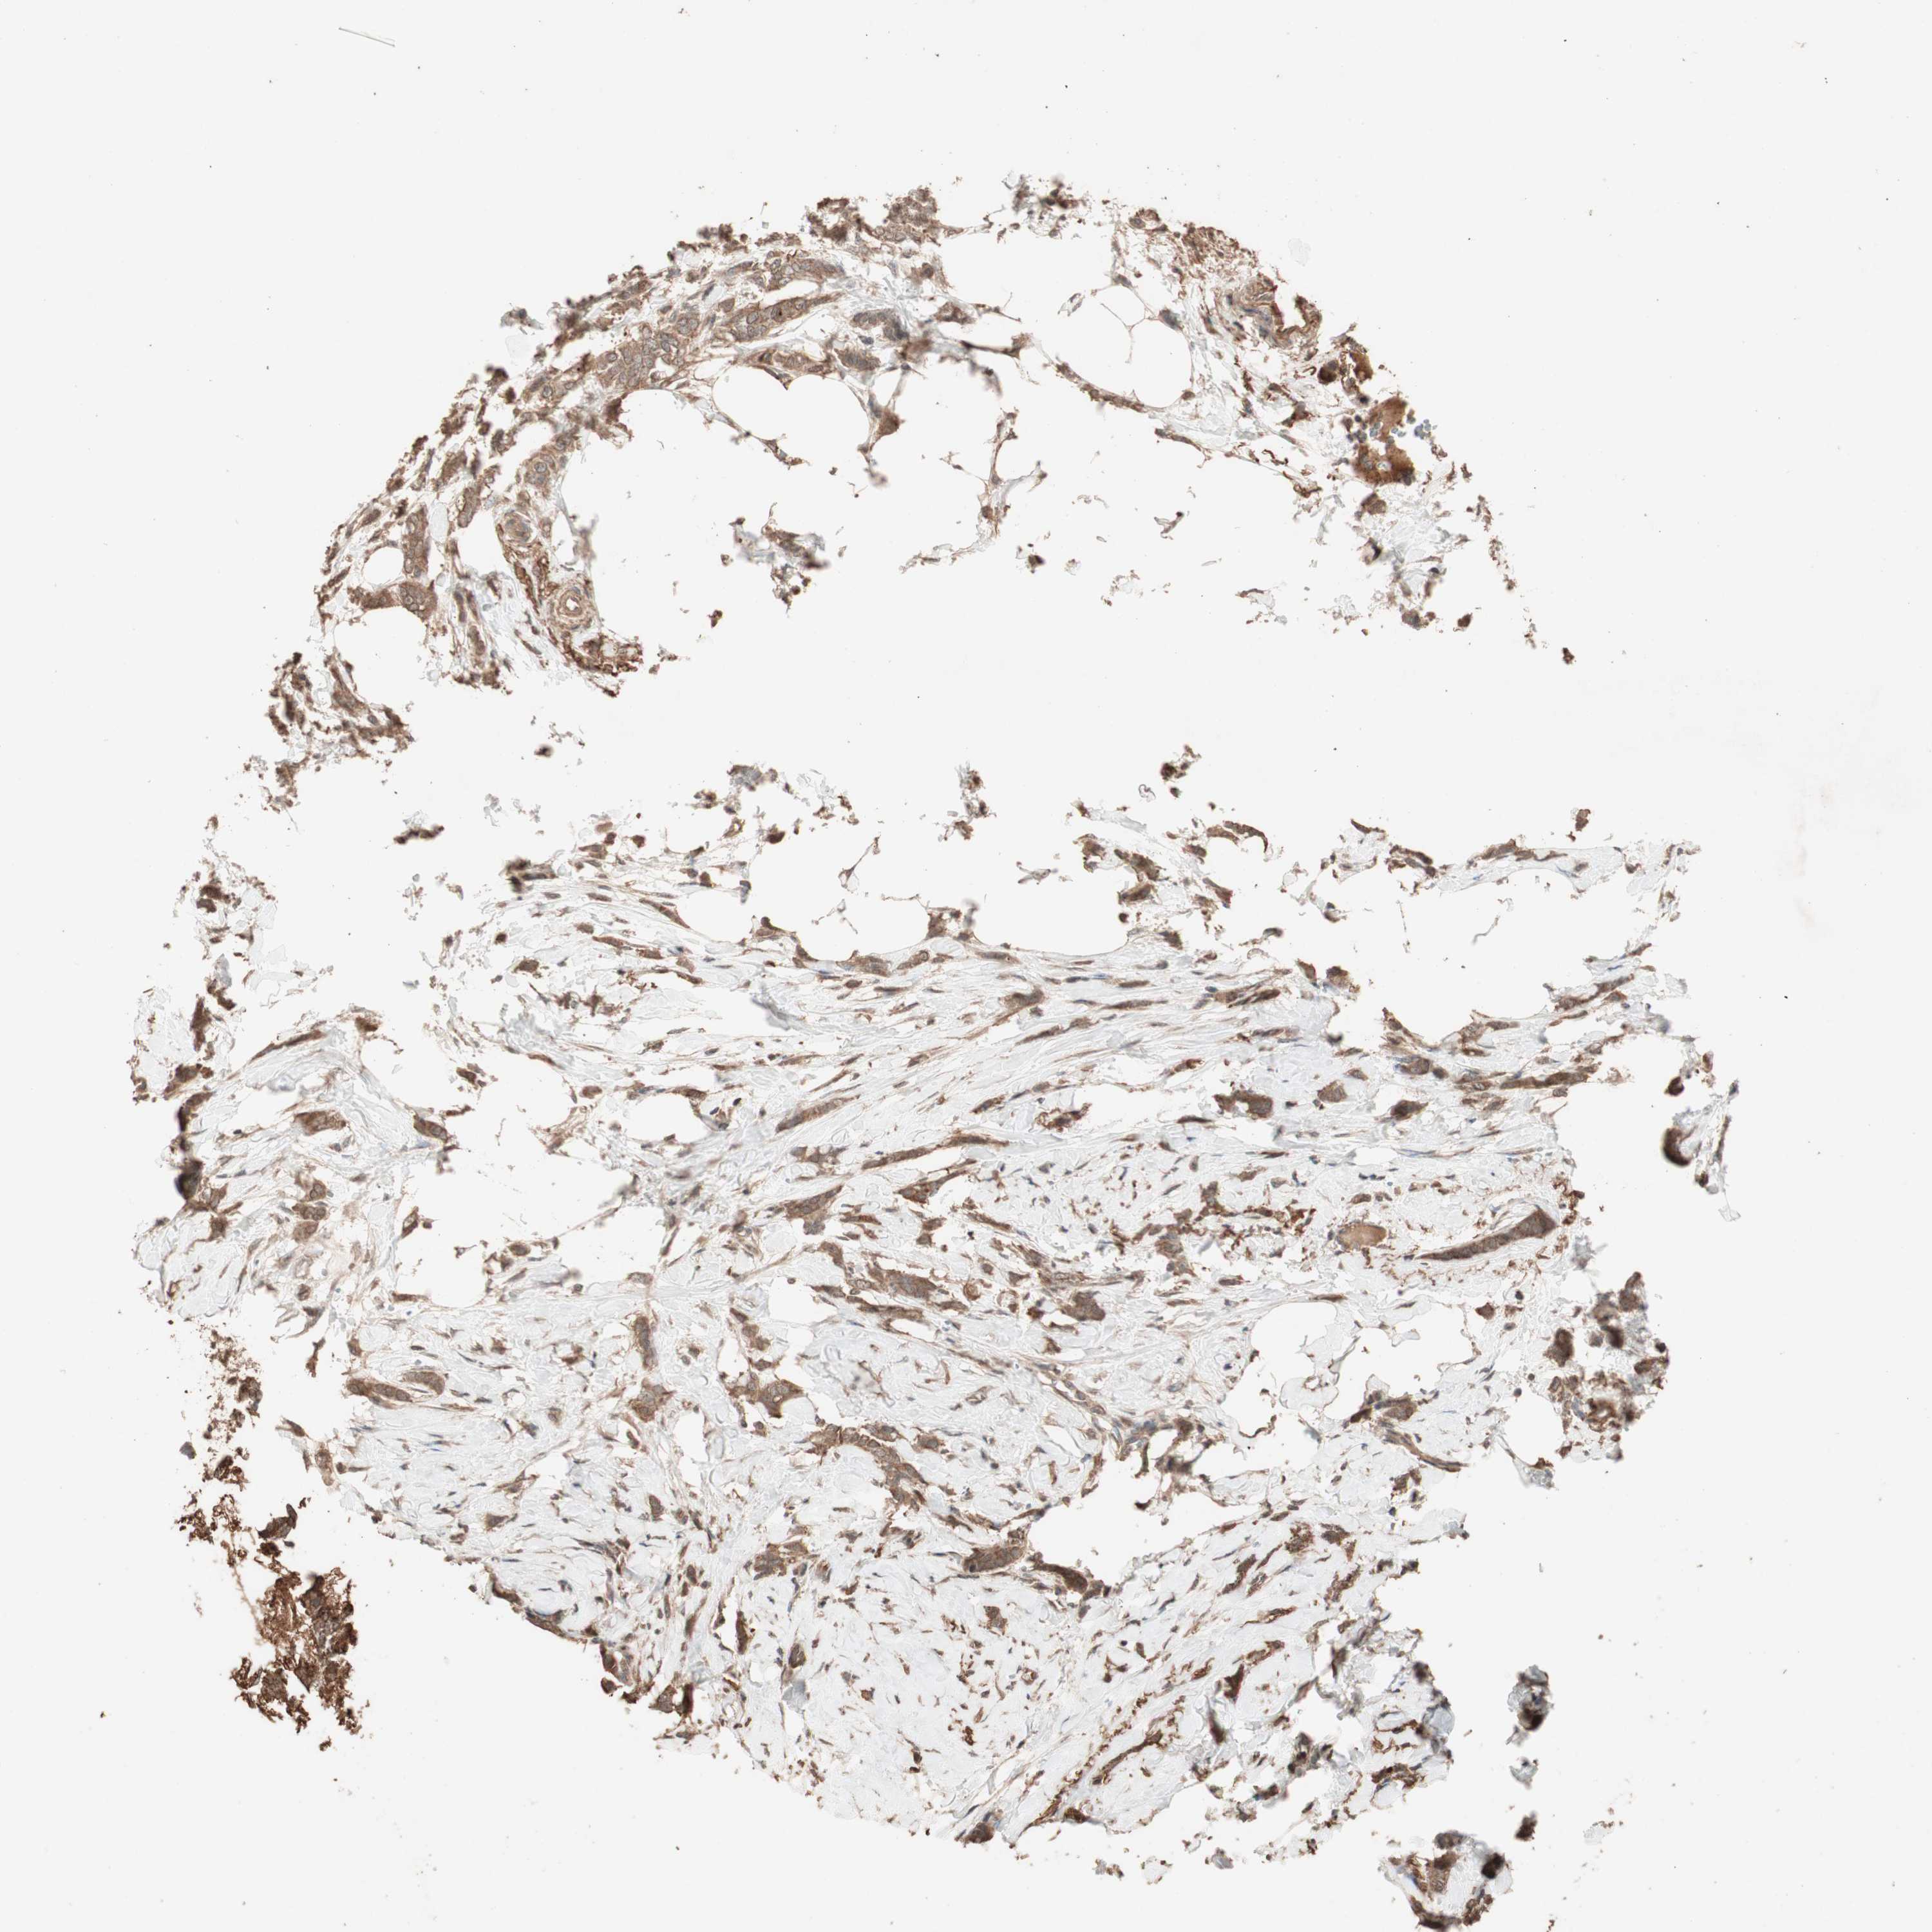

CANCER BREAST CANCER Show tissue menu

BRCA TCGA BRCA VALIDATION PROTEIN EXPRESSION